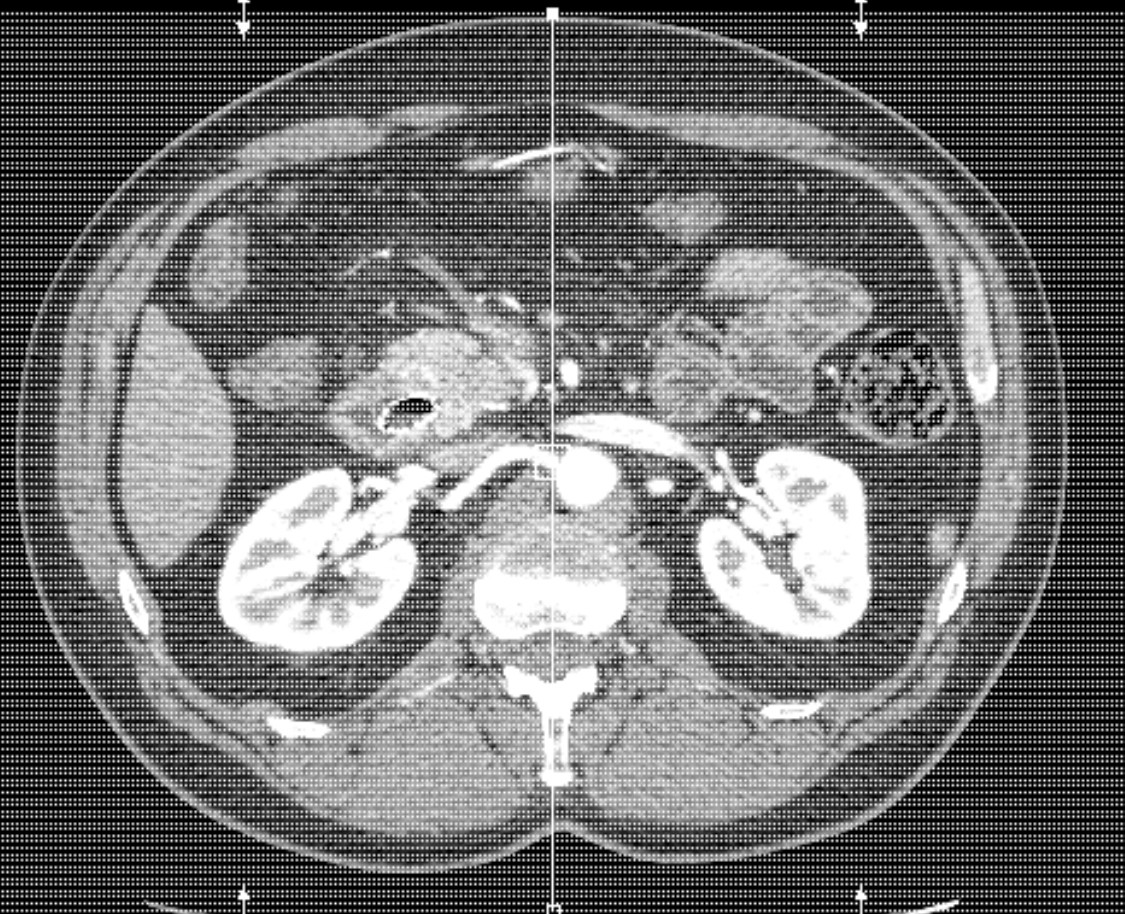

Good news…

It was January 8th, I made it to my scans at the other Mayo campus in east Scottsdale. They were CT scans with contrast so that means, as you are being imaged, they fill you with fluid that light up any areas of concern – they literally glow. This will have been the third time I have gone through this process and it is frankly one of the weirdest procedures I had ever experienced. The actual imaging is not a problem. You lay on the table, shirt off, pants down to your knees and hold your breath as you go back and forth through a big donut shaped x-ray machine. The weird part is the contrast. Once they release it into your veins, the familiar metallic taste of heparin and saline fills your mouth and throat. Then, it feels as if gallons of warm liquid fill you up inside, like a wave from your neck to your pelvis…surreal, gross, and just strange. The first time I had this done, the technician described it as ‘feeling like you wet yourself’…really? Regardless, I was excited to be done and couldn’t wait to get the results. Mayo is absolutely great about getting results out the same day. Usually, they are posted in the patient portal, but the scans required my oncologist to explain them so we made our way to his office. He came in smiling as usual, sat down and without hesitation, said “you’ve done very well” like I had just passed a history test. He explained that the tumor had shrunk to 1.7 cm from the 3.5 cm originally scanned when this all started – HALF!! It shrunk by half!Whatever I was going through physically and emotionally, it was all worth it to hear him say, ‘it shrunk by almost half!’ I was literally on cloud nine and Steph just looked shocked. He explained that we would stay the course with a few more infusions, then we would plan for radiation. As he left, Steph broke down in tears of joy, releasing a lot of pent up tension waiting for this moment. I had no doubt it was working. The poison they were injecting me with and the way it was making me feel, had to have some upside…it was working. We couldn’t get home fast enough to tell the kids: good news from the doctor, then a few days away for them to celebrate this milestone. There were shouts and tears and lots of happiness when we got home. We decided we were going to celebrate with cake! Allie went to the store for at least two bakery cakes and ice cream. The celebration was short lived.